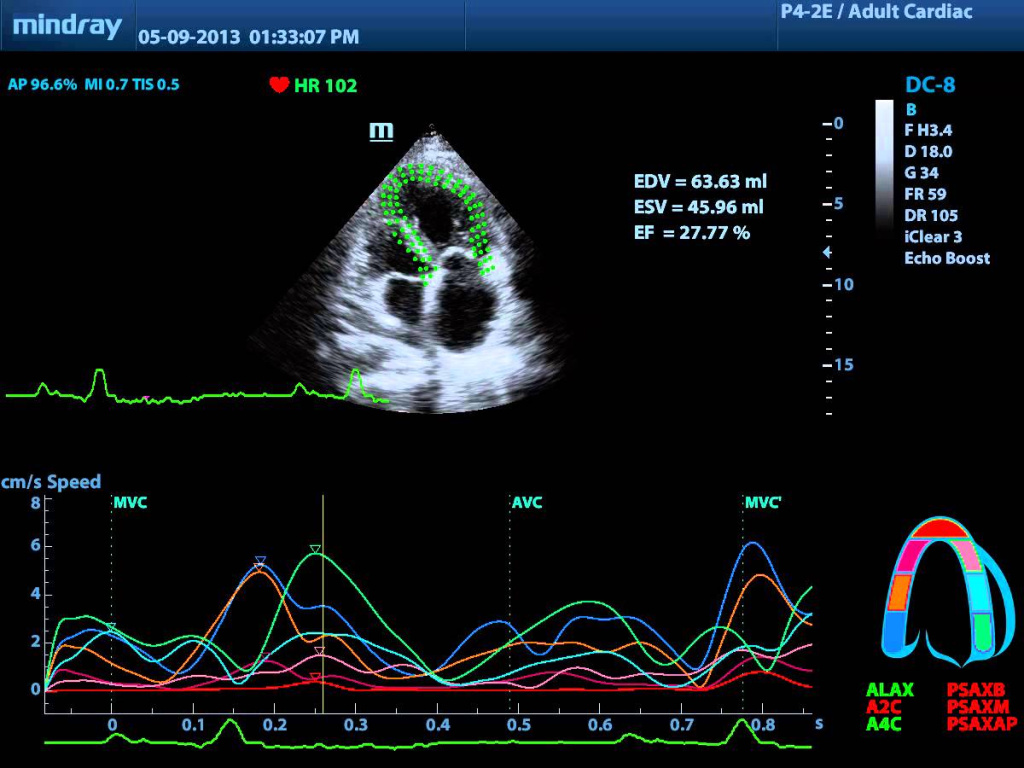

Технология визуализация вектора скорости движения миокарда применяется для определения величины и направления вектора скорости движения миокарда во время полного цикла сокращения сердца. Метод предоставляет информацию о состоянии целого комплекса физиологических функций сердца (пространственная деформация, скорость деформации, функции желудочков по длинной и короткой оси и пр.) и довольно легок в применении – единственным условием успешного применения методики является положение датчика при котором весь желудочек находится в зоне сканирования на протяжении времени совершения полного сердечного цикла.

Ниже представлено изображение, полученное с помощью прибора Mindray DC-8 в режиме Tissue Tracking и выводам Velocity vector на экран прибора.